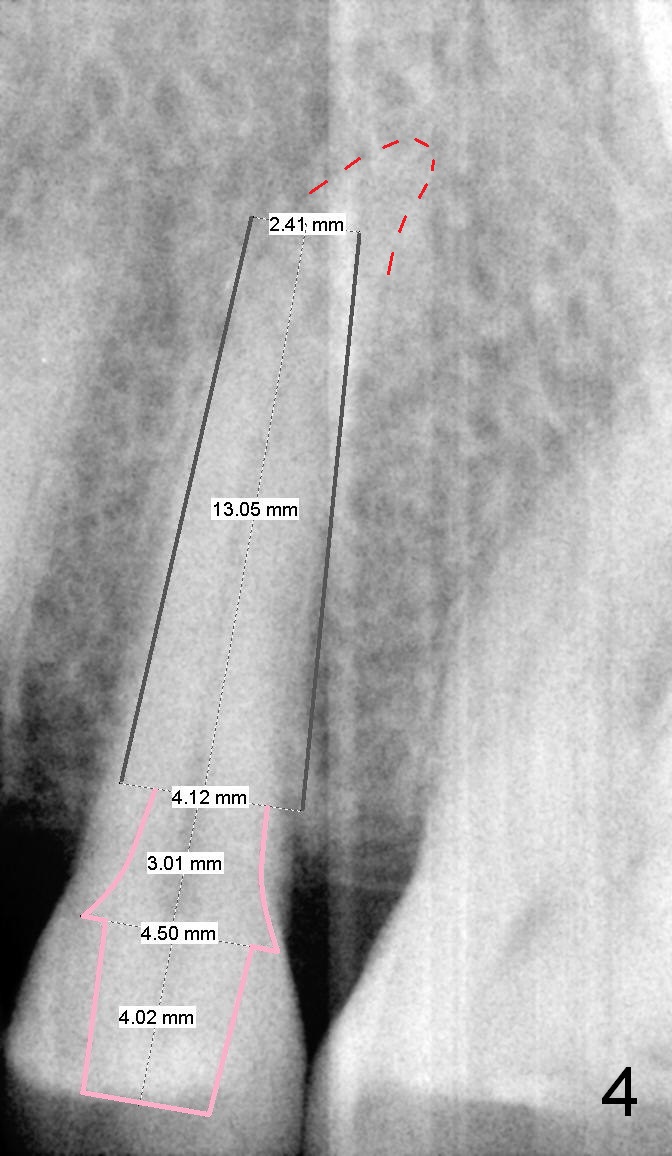

A 67-year-old lady (CC) has an implant at the site of #3, which replaces the fractured tooth (Fig.1). Recently the tooth #13 also fractures subgingivally (Fig.2). The tooth has a long and curved root. All of these suggest that the patient is a bruxer. The bone density is high. After extraction and placement of Clindamycin gauze in the socket, a 2 mm pilot drill is used to start osteotomy ~17 mm from the gingival margin, followed by 2.5 mm reamer ~ 17 mm, and 3 for 14 mm. If the socket looks small (mesiodistally), the goal is to place 4.1x14 (Fig.3) or 13 mm (Fig.4) implant. Otherwise use 4.5x17 mm Tatum tapered tap at 14 mm and plan to place a 4.5x13 or 14 mm implant. If it is difficult to insert an implant, use one size smaller drill from its original cassette or use 5x17 mm tap at 11 mm (to open up the entrance of the osteotomy). If the implant or tap is being deviated buccally while it is placed, use a Lindermann bur from Bicon Restorative plastic box to remove the bone from the palatal wall. When the side-cutting drill is cleaned, keep it in the Bicon Surgical Cassette. If the bone density turns out to be low, osteotomy depth will be 20 mm instead (Fig.5). When the flutes of 2.5 and 3 mm reamers collects bone particles, the bone density is high.